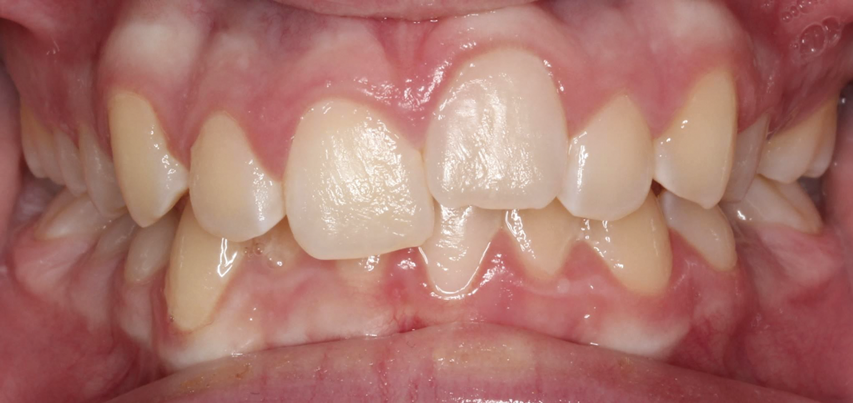

Fig 3. Implants were placed in a 20-year-old female patient in the Nos. 7 and 11 sites with a pontic replacing No. 10.

Fig 4. A 15-year postoperative photograph of the patient in Fig 3 illustrates the significant infraocclusion of the implants compared to the natural teeth. Also, note the blue tissue discoloration over implants Nos. 7 and 11.

A third risk of using an implant to replace a missing lateral incisor is the continued vertical growth of the alveolar bone and eruption of the teeth adjacent to the implant.9,10 Traditionally, it has been taught that an implant can be safely placed when alveolar bone growth is confirmed complete with serial radiographs. However, numerous studies call that rule into question.11-16 Bernard et al evaluated vertical changes in teeth adjacent to implants in a young group of patients (15.5 to 21 years) and in a mature group (40 to 55 years), over a mean time of 4.2 years.17 In the young group, infraocclusion of the implant crowns ranged from 0.1 mm to 1.65 mm, while in the mature group the infraocclusion of the implant crowns ranged from 0.12 mm to 1.86 mm. An example of infraocclusion that occurred in a young implant patient over time is depicted in Figure 3 and Figure 4. Based on classic literature as cited here, it seems prudent to delay the placement of implants in high-risk areas, such as the maxillary lateral incisor region, for as long as possible or perhaps avoid it altogether.